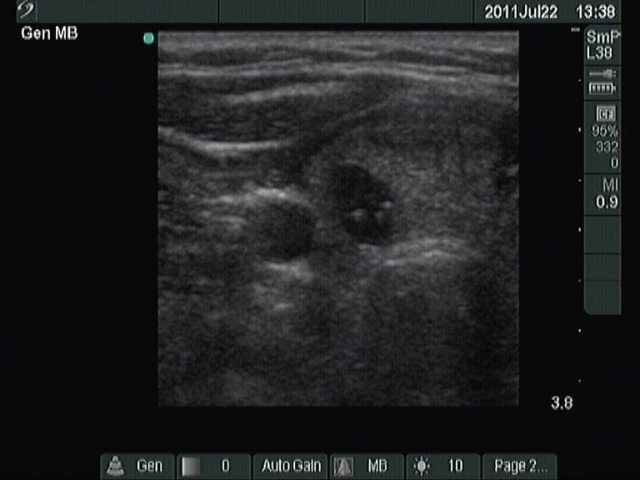

Benign hyperplastic nodule (histological diagnosis) - case 2 |

The bright granules lack the dorsal narrowing tail and there are no coexisting similarly bright lines, therefore these granules correspond to punctate echogenic foci.